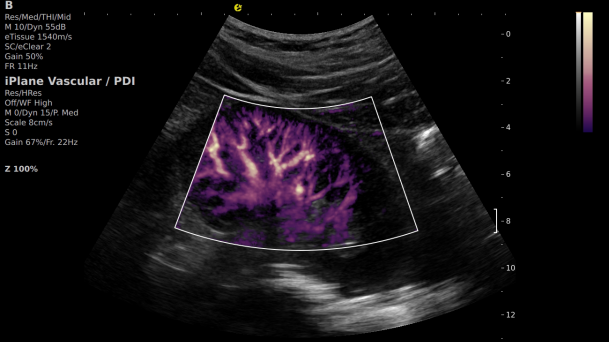

1) 基于OmniSound?平面波超快速平台,超声信号采集帧频提高了200倍(25000Hz)。

2) 可检测20-50μm级细小血管低速血流信号,能看清头发丝1/2粗细的微血管;

3) 通过血管指数(VI)定量评估局部血管密度,以定量化数据实时监测血流灌注情况,预判肾功能恢复情况;

开启肾移植微观视界 | 银河官网黑科技为您“移”路护航(图6)

超微视血流显像显示肾脏五级血管

开启肾移植微观视界 | 银河官网黑科技为您“移”路护航(图7)

微米级超高分辨率血流信号显像

开启肾移植微观视界 | 银河官网黑科技为您“移”路护航(图8)

肾脏的灌注评估,RI/VI量化数据

开启肾移植微观视界 | 银河官网黑科技为您“移”路护航(图9)

开启肾移植微观视界 | 银河官网黑科技为您“移”路护航(图10)

开启肾移植微观视界 | 银河官网黑科技为您“移”路护航(图11)

超微视血流显像评估肾移植术后灌注情况

这一项无创、无辐射操作简便且无需造影剂的黑科技,相当于用"高速摄像机"记录血液细胞的运动轨迹,让血管并发症"无处遁形。